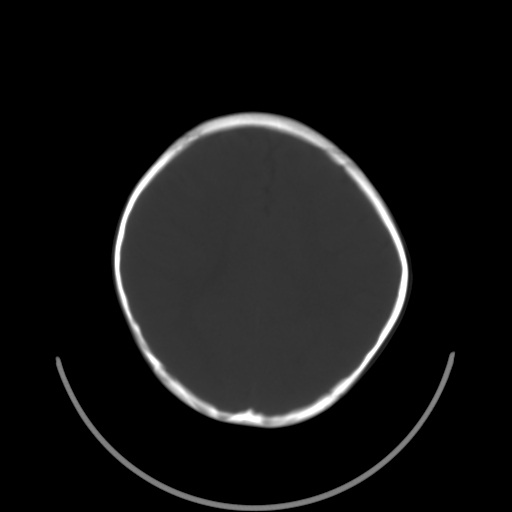

以下是引用深泽交通医院在2009-10-16 8:25:00的发言:[br]右眼环出血伴异物

以下是引用卜一在2009-10-16 15:01:00的发言:[br]右眼球挫裂伤伴异物!

以下是引用拾荒者在2009-10-17 18:38:00的发言:[br]鼻面部皮下积气,右侧睑缘及眼球壁高密度异物影,左侧眼球壁晶状体内侧缘处是圆形低密度影。低密度异物?应提请眼科医生注意。